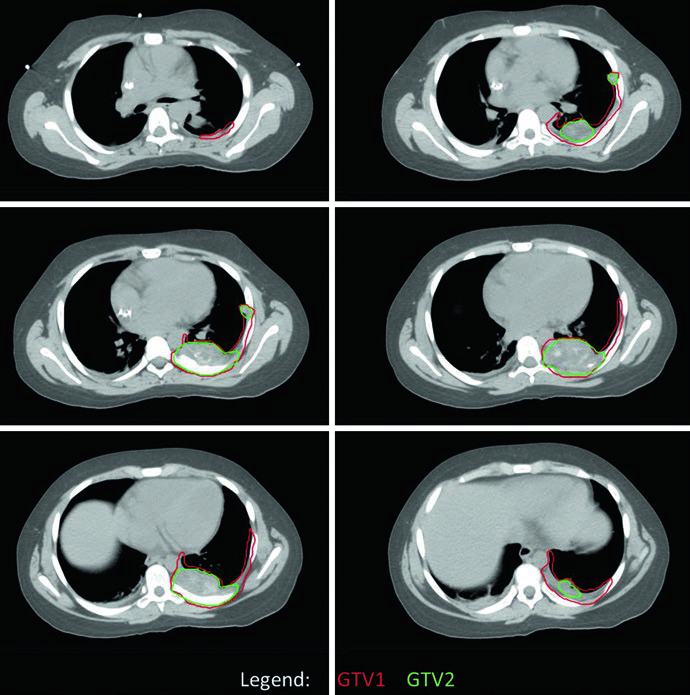

O planejamento no EWS utiliza dois conjuntos de volumes: um baseado na extensão da doença ao diagnóstico (GTV1/CTV1) e outro definido pela doença residual pós-quimioterapia e, eventualmente, pós-cirurgia (GTV2/CTV2). As margens adicionadas aos CTVs para incerteza de posicionamento resultam nos respectivos PTVs.

Um ponto prático central é o manejo do GTV1 quando o tumor se estende para cavidades corporais. Se a imagem pré-tratamento mostra tumor “empurrando” pulmão ou vísceras pélvicas — sem invasão direta — o GTV1 pode ser adaptado após a quimioterapia de indução para refletir a regressão tumoral nesses espaços. Essa adaptação aparece claramente no caso de EWS pélvico, onde o nível inferior não apresenta doença residual (GTV2) e a extensão do GTV1 para a pelve foi reduzida para compensar a resposta à quimioterapia. O PTV1 recebeu 45 Gy e o PTV2 recebeu 10,8 Gy adicionais, totalizando 55,8 Gy.

No caso de EWS de parede torácica, a simulação com TC de quatro dimensões (4DCT) foi realizada para capturar a excursão respiratória completa dos volumes-alvo. O tumor original ocupava a metade posterior do hemitórax esquerdo, mas o GTV1 foi adaptado para refletir o “pushing” tumoral no espaço agora ocupado por pulmão normal. A cobertura dos sítios de contato e envolvimento originais foi mantida. Da mesma forma, PTV1 recebeu 45 Gy e PTV2 um boost adicional de 10,8 Gy.